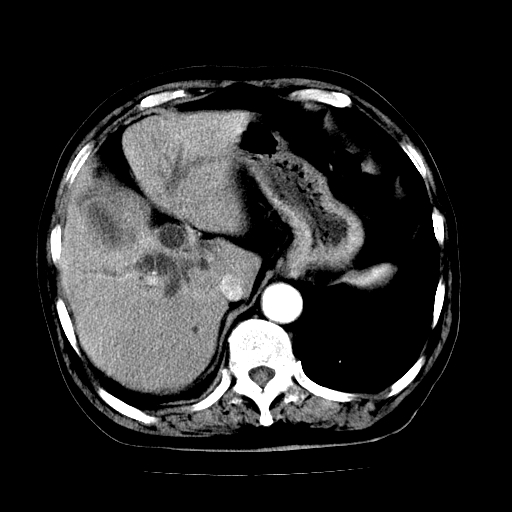

男,71岁,皮肤黄染四天。

肝内外胆管及胆总管上段扩张,考虑为梗阻所致,建议mrcp检查。

考虑胆总管癌并肝内外胆管扩张。

胰腺上端胆总管内见软组织影,强化不明显,结合临床,还是考虑低位梗阻性黄疸,胆总管癌可能性大